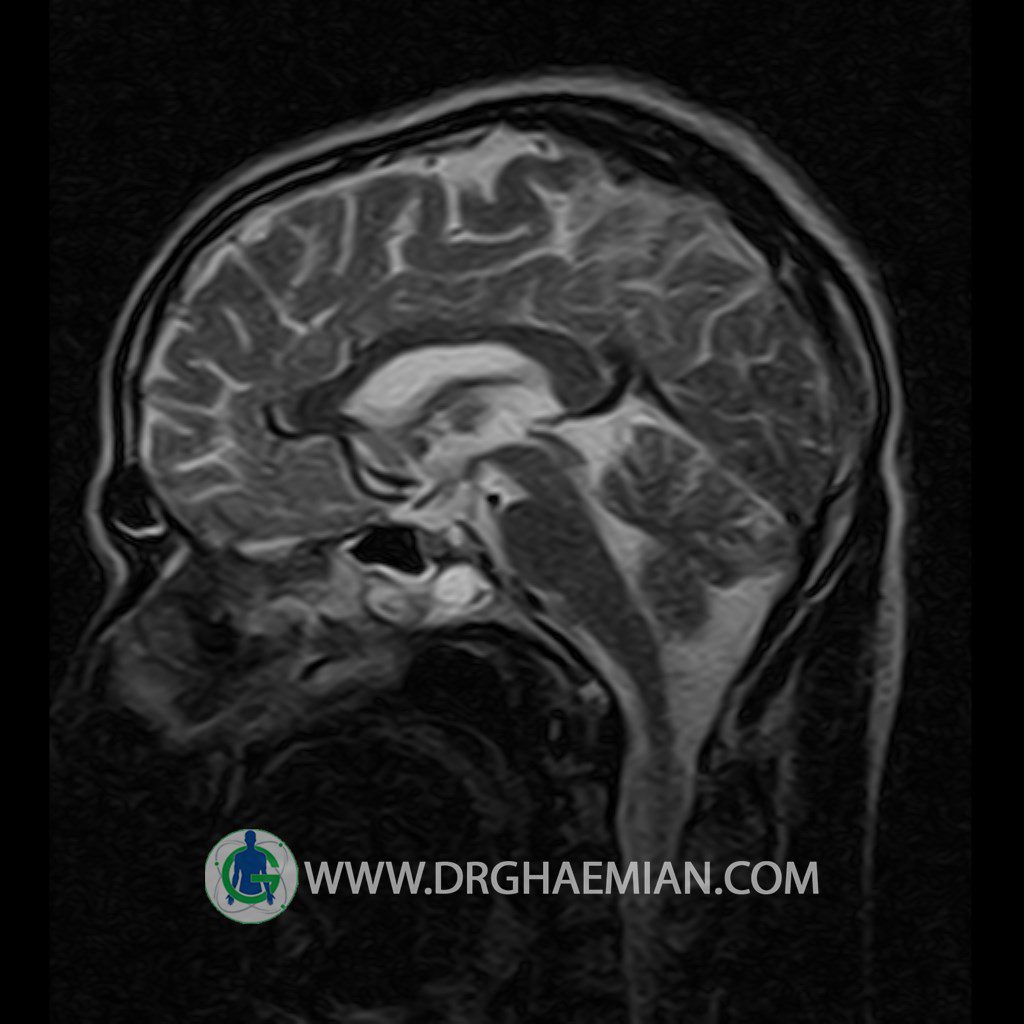

پزشکان اغلب از تصویربرداری ام آر آی برای تشخیص و درمان عارضه های پزشکی که فقط با استفاده از اشعه ایکس یا میدان مغناطیسی و امواج رادیویی قابل مشاهده است، استفاده می کنند. دستگاه ام آر آی تصاویر دقیق از ساختار های داخلی بدن ایجاد می کند. در این کیس یک میکروآدنوم در هیپوفیز بیمار مشاهده می شود.

HYPOPHYSIS MRI

(with and without contrast)

Technique: Axial , coronal T1 , Axial , coronal , sagittal T2 , Axial, coronal T1 post Gd & 64 dynamic thin coronal slices.

REPORT :

The infundibulum is centered and of normal size .

The optic chiasm and suprasellar spaces appear normal .

The cavernous sinus and imaged portions of the internal carotid artery and carotid siphon are unremarkable .

Evaluable portions of the neurocranium show no abnormalities .

The sphenoid sinus is clear and pneumatized .

Imaging of the hypothalamus after contrast medium administration was normal.

– Small hypoenhancing mass lesion ( 3 x 4 mm ) in posterior of pituitary stalk suggestive for micro adenoma

– Mucosal thickening in ethmoid & maxillary sinuses

is seen